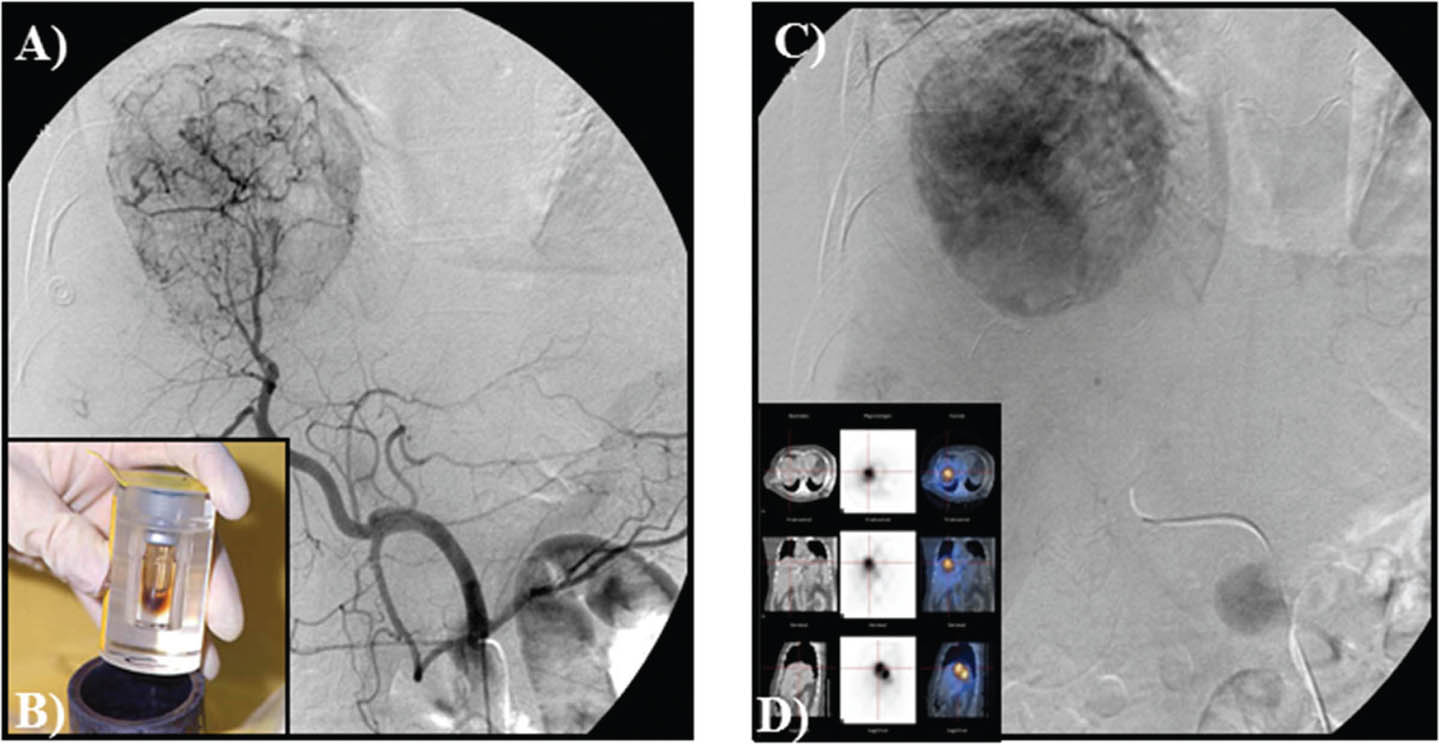

Fig 11

Figure 11. Y-90 embolization for hepatocellular carcinoma. A. Selective angiography of the liver and detection with obliteration of systemic shunts is performed. B, C and D. Micro-spheres then are embolized to the liver with no vessel occlusion.